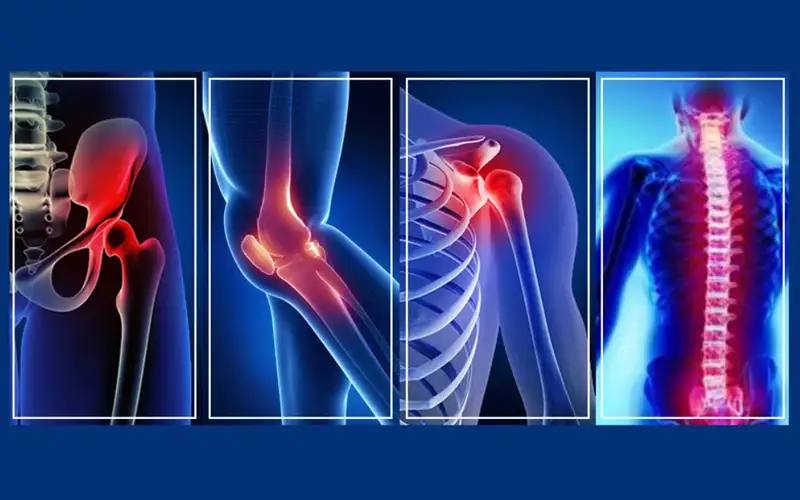

ارتوپدی (Orthopedics) شاخهای از پزشکی است که به بررسی، تشخیص، درمان و پیشگیری از بیماریها و آسیبهای سیستم اسکلتی عضلانی بدن میپردازد. اسکلتی عضلانی شامل استخوانها، مفاصل، عضلات، تاندونها، رباطها و اعصاب است. یعنی اگر استخان، مفاصل یا عضلات شما دچار مشکل یا بیماری شود، باید به یک دکتر ارتوپد مراجعه کنید.

همانطور که گفتیم ارتوپدی چیست و متخصصان ارتوپدی به تشخیص، درمان و پیشگیری از مشکلات اسکلتی-عضلانی میپردازند. این مشکلات شامل بیماریهای مفصلی، مشکلات ستون فقرات، شکستگیها، آسیبهای ورزشی و بسیاری از موارد دیگر است. برخی از شایعترین بیماریها که متخصص ارتوپدی دانش درمان آنها را دارد، عبارتاند از:

آرتروز که به اسم استئوآرتریت نیز شناخته میشود یکی از رایجترین بیماریهای مفصلی است که در اکثر افراد در سنین بالا ظاهر میشود. در این بیماری، غضروفی که بین مفاصل قرار دارد، به تدریج تخریب شده و باعث درد، خشکی و کاهش انعطافپذیری مفصل میشود. آرتروز بیشتر در زانو، لگن، دست و ستون فقرات دیده میشود. برای درمان آرتوروز متخصص ارتوپدی بسته به شرایط بیمار، مصرف داروهای ضدالتهابی، ورزشهای مخصوص، فیزیوتراپی و در موارد شدید، جراحی تعویض مفصل را توصیه میکند.

شایعترین مشکلات ستون فقرات دیسک کمر و گردن است. این مشکل به دلیل بیرونزدگی یا پارگی دیسک بین مهرهها ایجاد میشود. این وضعیت باعث فشار بر اعصاب شده و درد شدیدی در کمر، گردن یا حتی پاها و دستها ایجاد میکند. به همین دلیل افرادی که دچار دیسک کمر یا دیسک گردن میشوند، علاوه بر اینکه کمر یا گردن آنها درد شدیدی میگیرد، ممکن است درد را در دستها یا پاها حس کنند. عواملی مانند بلند کردن اجسام سنگین، نشستنهای طولانیمدت و افزایش سن نقش بسیار مهمی در مشکلات ستون فقرات دارد. درمان این مشکلات توسط متخصص ارتوپدی انجام میشود که شامل فیزیوتراپی، تجویز داروهای ضدالتهابی و در موارد حاد، جراحی است.

دررفتگی مفاصل یکی دیگر از مشکلات شایع است که توسط پزشک ارتوپدی درمان میشود. دررفتگی معمولا در شانه، زانو یا لگن رخ میدهد و باعث درد شدید میشود. دررفتگی باید سریعا توسط متخصص ارتوپدی جااندازی شود و پس از آن بیمار باید مدتی استراحت کند تا مفصل به حالت طبیعی خود بازگردد. در برخی موارد با تشخیص متخصص ارتوپد، آسیبهای ناشی از دررفتگی به قدری شدید است که نیاز به جراحی دارد.